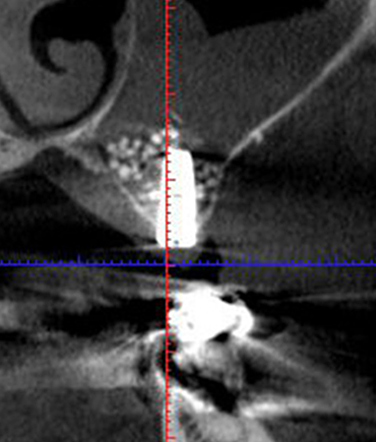

埋入後のCT像

After

インプラント治療を検討されて、「骨が少ないからインプラントができませんと・・・」と断られた方は、あきらめないで下さい。サイナスリフトという方法を用いれば、インプラントは可能です。